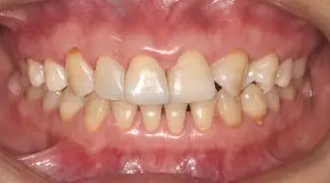

術(shù)前微笑照

病例分享|復(fù)合樹脂微創(chuàng)美學(xué)修復(fù)關(guān)閉上前牙間隙

術(shù)前全牙弓咬合照